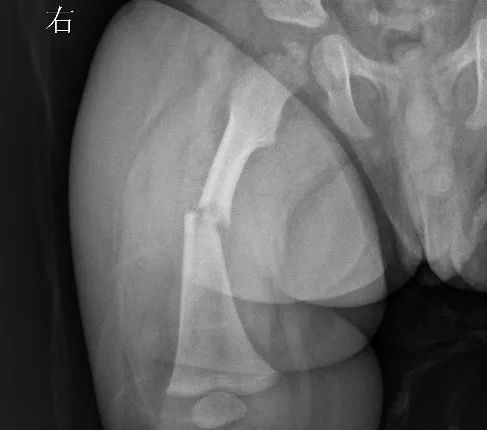

接诊的急诊骨科医生张明仔细检查孩子的双腿结合拍片结果诊断,右侧大腿股骨骨折。随即转到小儿骨科病区。由于孩子太小无法手术,只能先进行至少三周的牵引复位,再打石膏做进一步治疗。